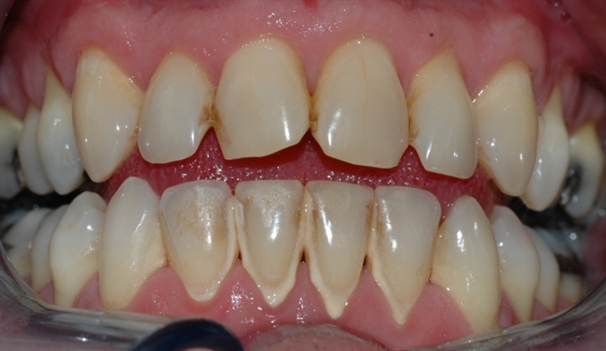

perio stor 1

Bildet viser tilsynelatende normale tannkjøttsforhold ved tenner i underkjeven.